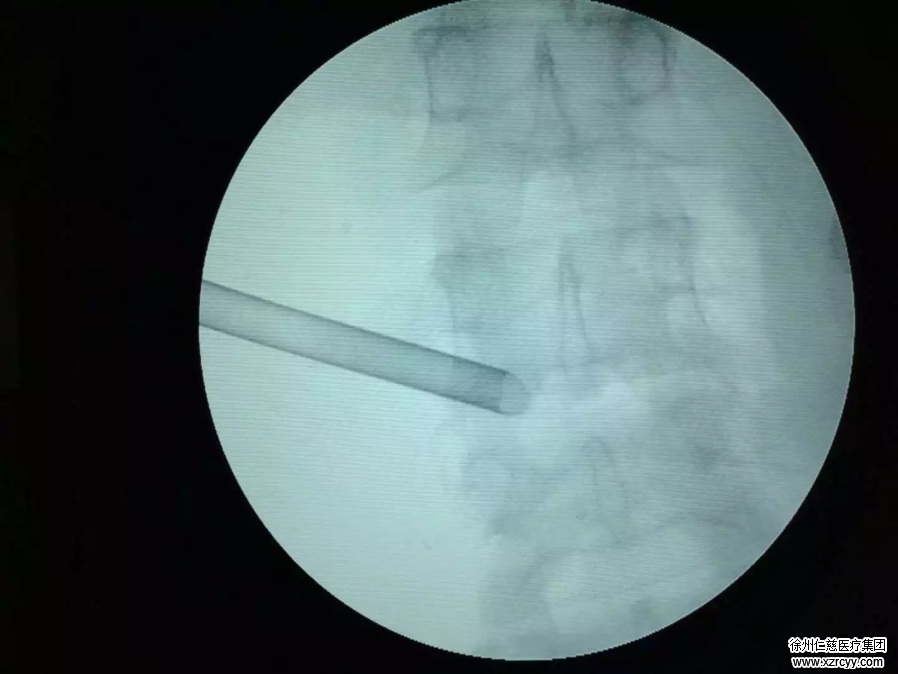

20岁的小赵是一名在校大学生,喜欢长期伏案打电脑游戏。谁知在一次打篮球后,小赵发现不仅他患上了腰痛的毛病,而且右下肢也愈发疼痛,有麻木感,经外院保守治疗疗效欠佳。由于即将返校学习,为此小赵在亲友的推荐下来到betway在线登陆疼痛科求医,疼痛科主任范后宝通过CT检查发现,造成小赵病痛的原因是长期伏案使4、5节腰椎内的髓核已经从纤维环中被压迫出来,可以通过微创手术解除痛苦。后经医生详细讲解微创手术的好处,小赵这才点头答应。入院不久,医生就尽快安排小赵做完术前检查,后在局麻下通过脊柱内镜直接把椎间盘髓核摘除,整个手术切口竟然是个直径只有0.7厘米的通道。

“手术中,我就觉得疼痛减轻了。当晚,我就可以坐起来了,术后第二天就可以自己下床上厕所。”小赵表示,这跟他以前听说的腰椎间盘手术全然不同。